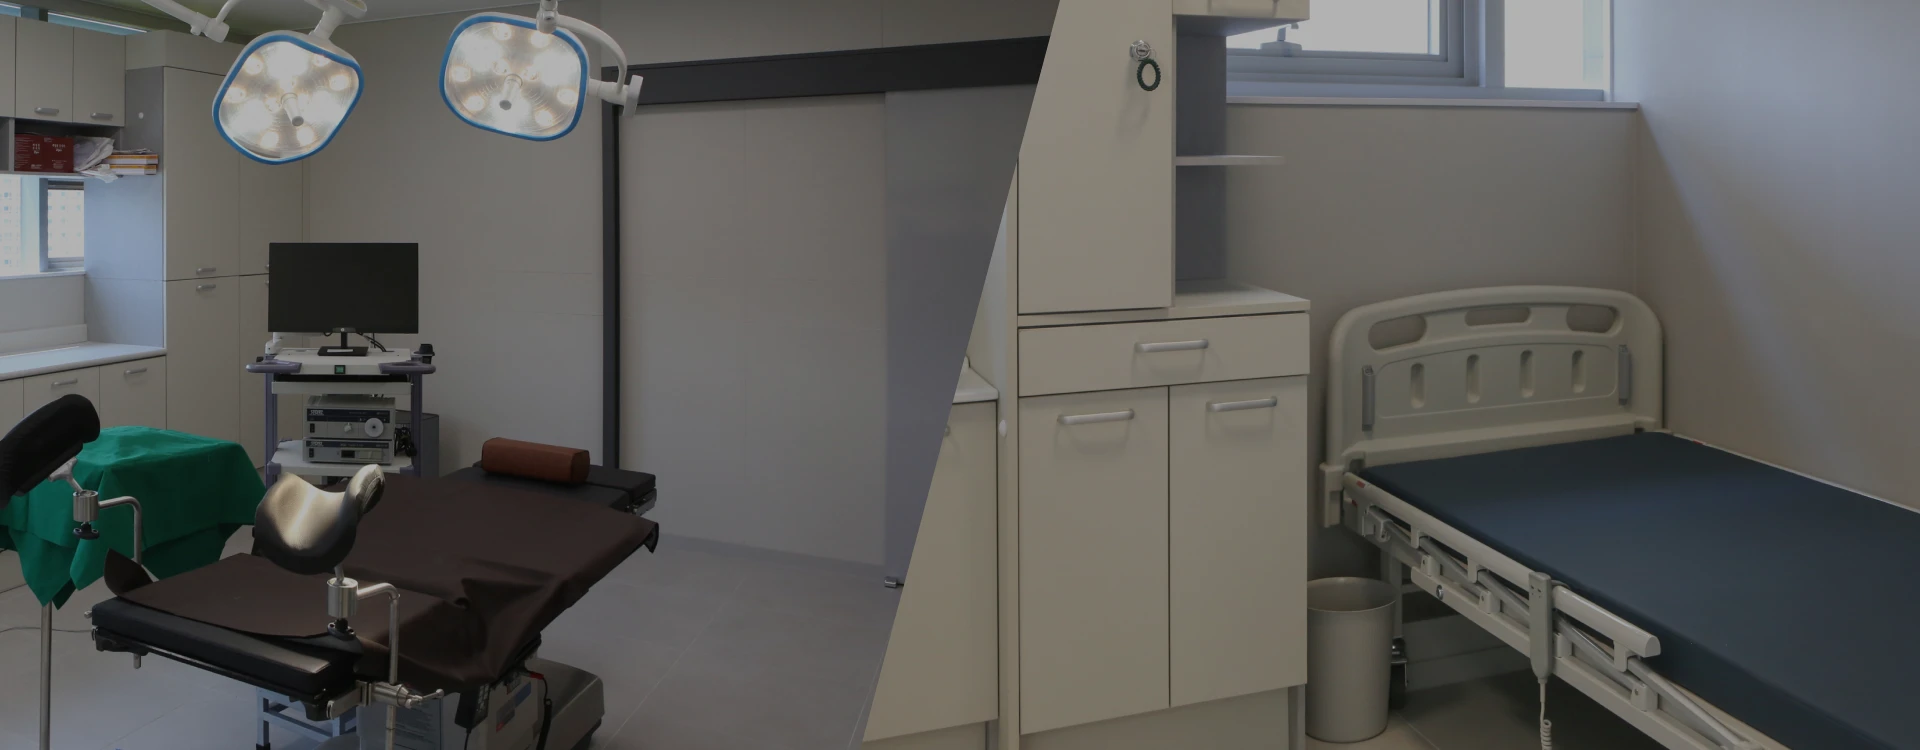

OTH UROLOGY CLINIC

둘러보기